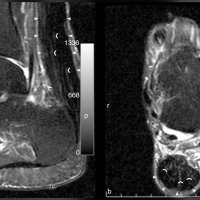

MRI shows focal thickening of the tendon with increased AP diameter, loss of the normal anterior concavity of the tendon with speckled appearance of the tendon, hyperintense on T1- and T2-weighted images.